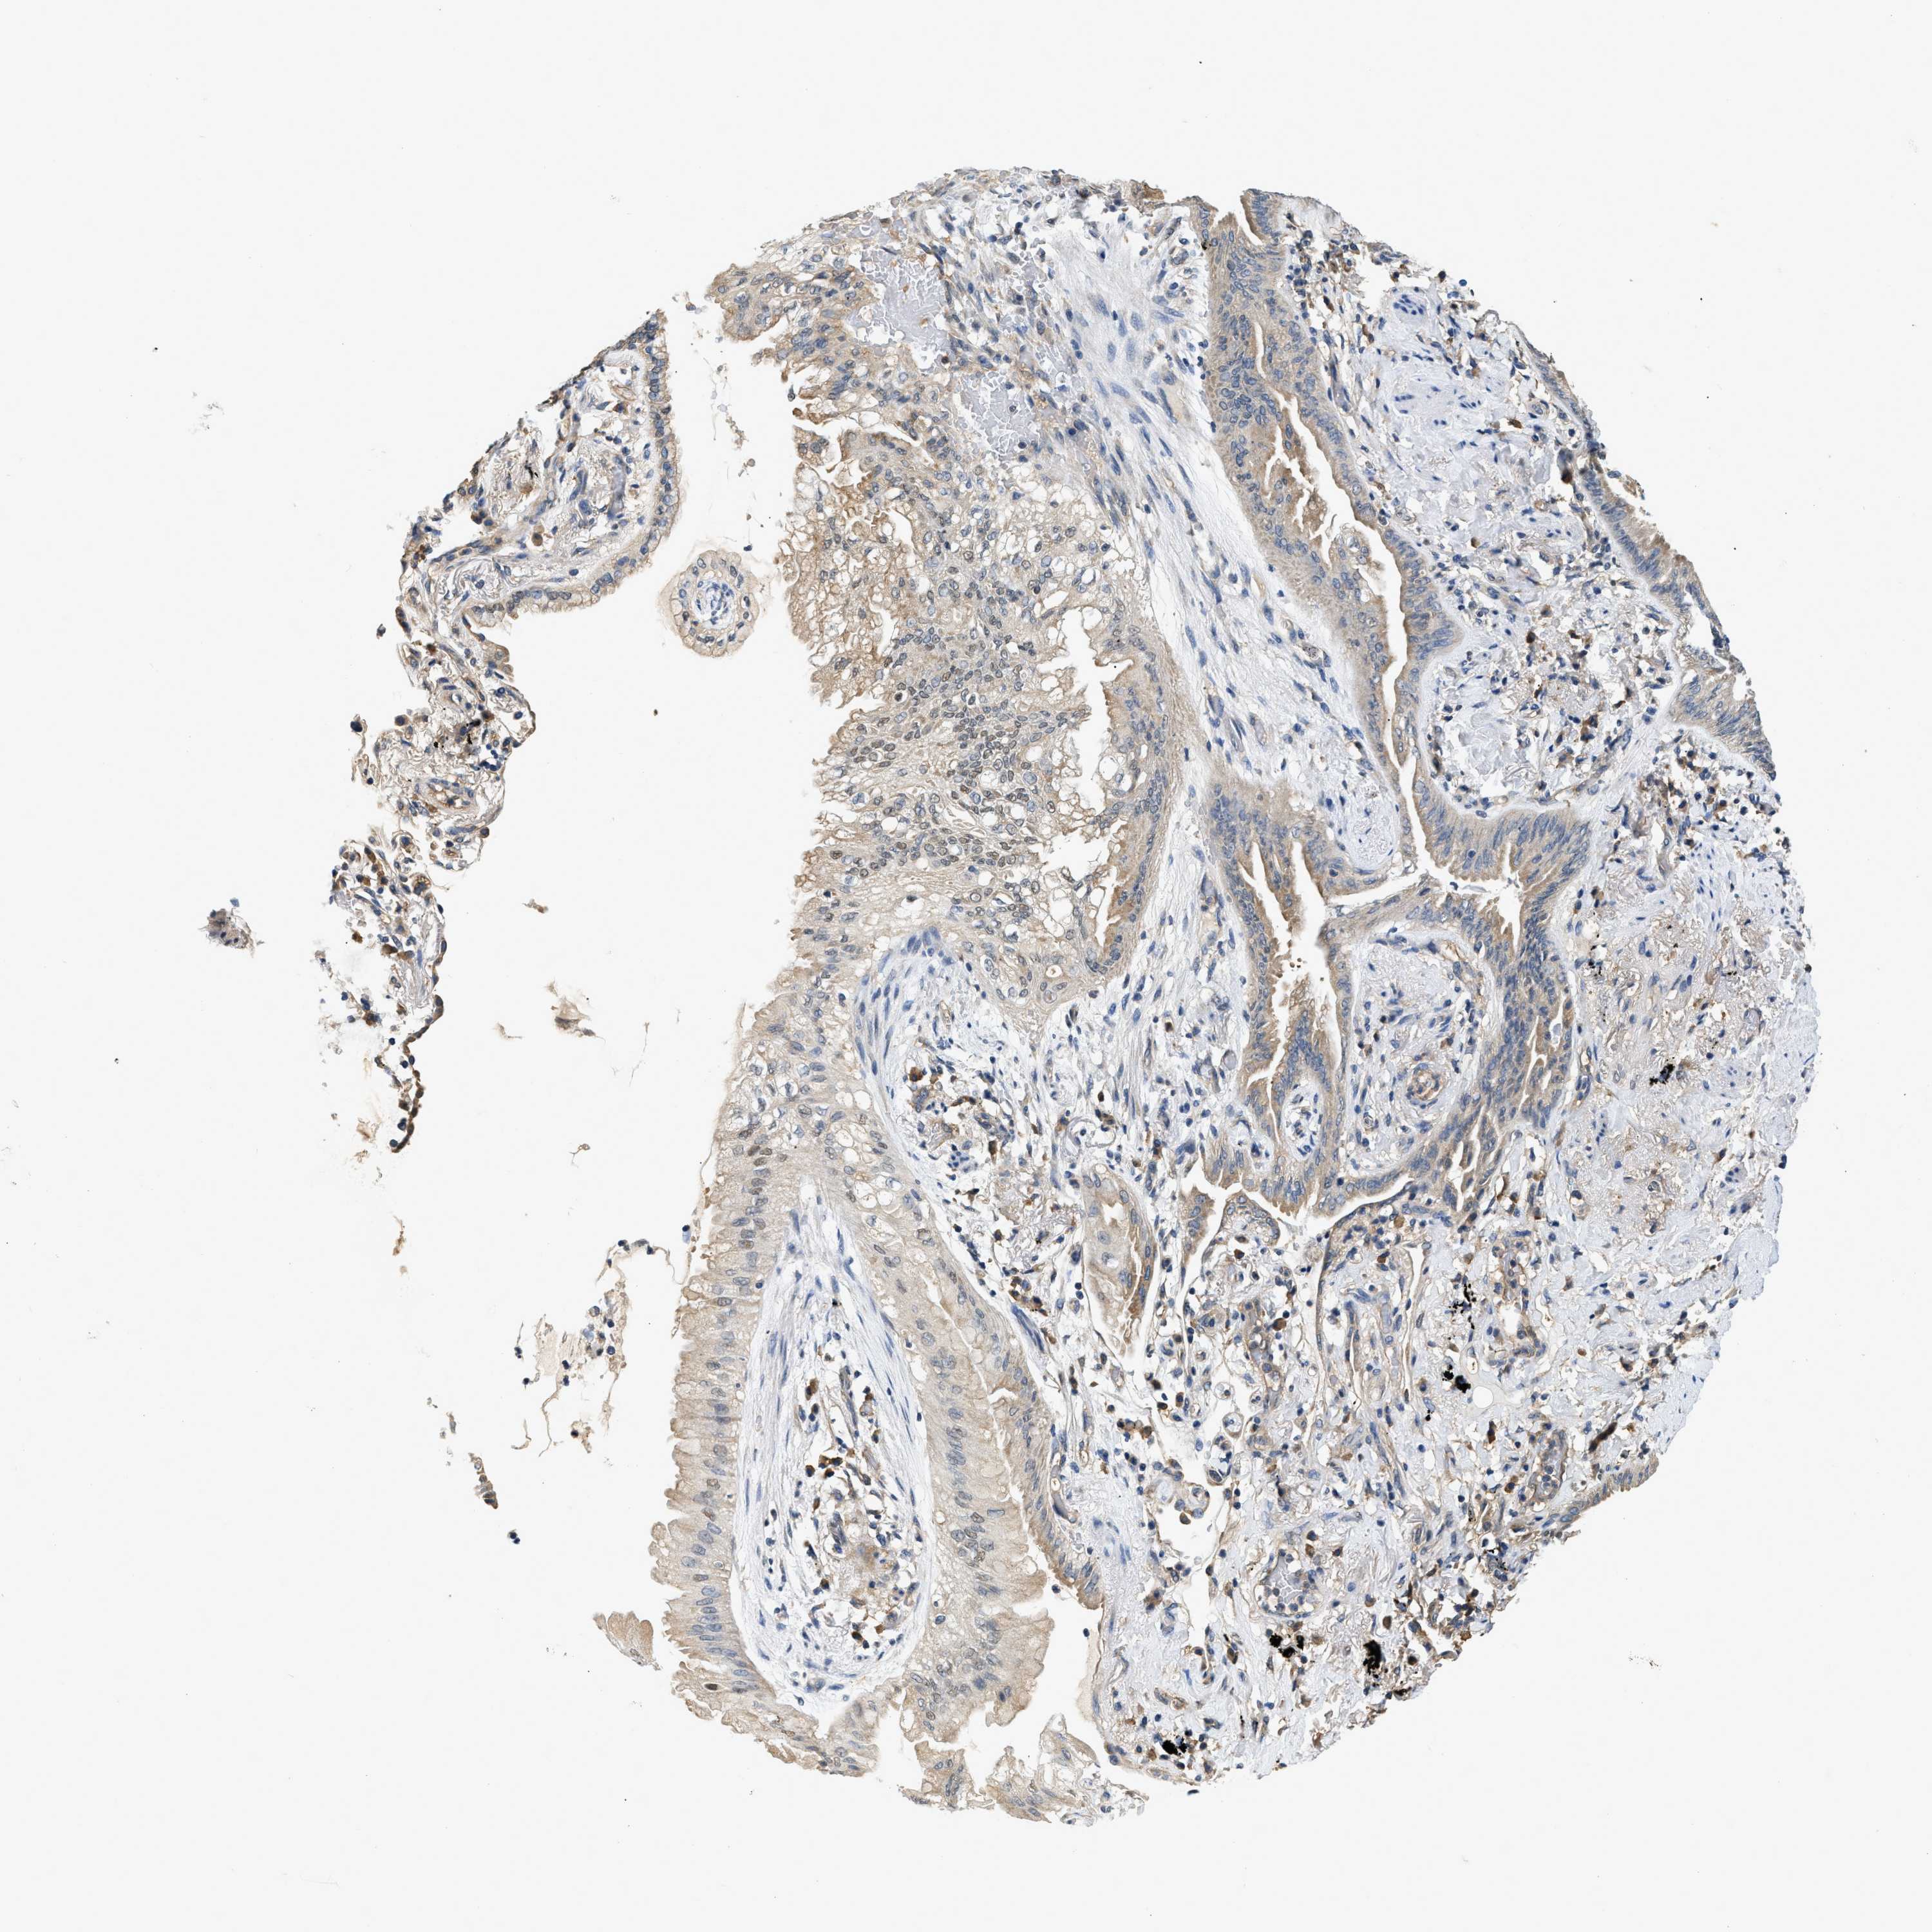

BCL7C

• BCL7C

CANCER LUNG CANCER Show tissue menu

Lung cancer

Human cancer

Lung adenocarcinoma

Lung squamous cell carcinoma